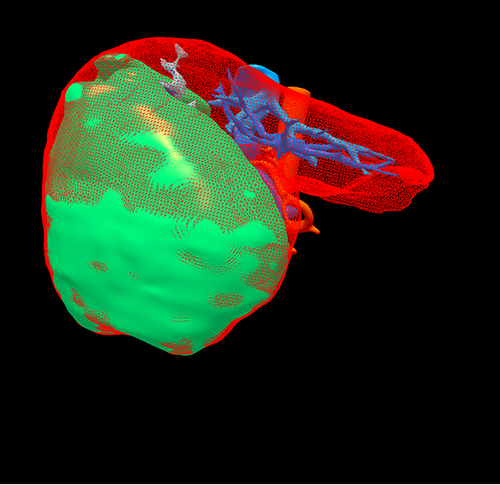

右肝癌---右三肝切除